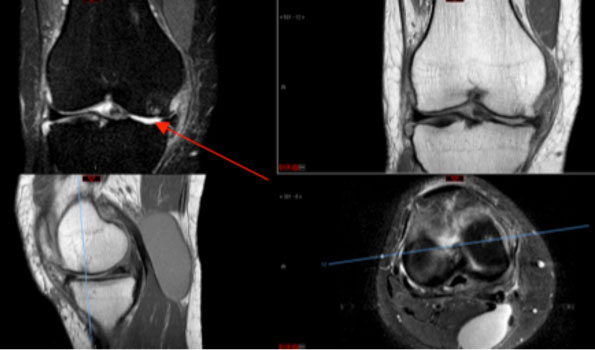

Hohe Tibiaosteotomie (Unterschenkel) links.

Beispiel einer hohen Tibiaosteotomie mit Tomofix-Plattensystem. Die oberen Bilder entsprechen der MRI-Bildgebung, im oberen linken Bild ist durch den roten Pfeil ein Knochenödem am Oberschenkel markiert. In der Ganzbeinaufnahme ist zu sehen, wie aus dem O-Bein ein X-Bein wurde. Die mechanische Beinachse (rot) wurde vom Innengelenk in das Aussengelenk des Knies verlagert